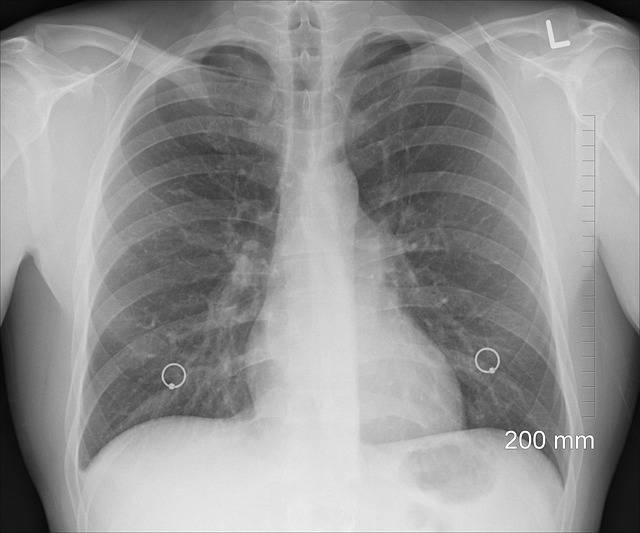

„Godišnje se u Severnobačkom okrugu registruje najviše oko dvoje obolelih od tuberkuloze koja spada u veoma rezistentan mikroorganizam, a najopasniji je tuberkulozni meningitis jer vakcina za odrasle ne postoji“, izjavio je za Magločistač epidemiolog Zavoda za javno zdravlje Subotica, dr Nebojša Bohucki.

„Bilo bi dobro da postoji vakcina kojom bi odrasle mogli vakcinisati. Današnja vakcina koja se koristi od 1921. godine čuva decu do pete godina života da nemaju komplikacije, od kojih je najteža – tuberkulozni meningitis. To uđe u pluća svakome ko udahne, ko je pored nekoga ko kašlje i kija, a dešava se da obole osobe koje puše i piju“, ističe.

Dr Bohucki ističe da godišnje 10 miliona ljudi u svetu oboli od tuberkuloze, a da 1,6 miliona ljudi umire od ove bolesti.